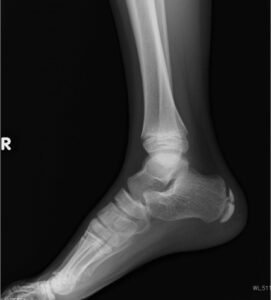

来院時には、レントゲンで骨の状態を確認したり、エコーで軟部組織を見たり、必要に応じて神経学的検査を行うケースもあるようです。